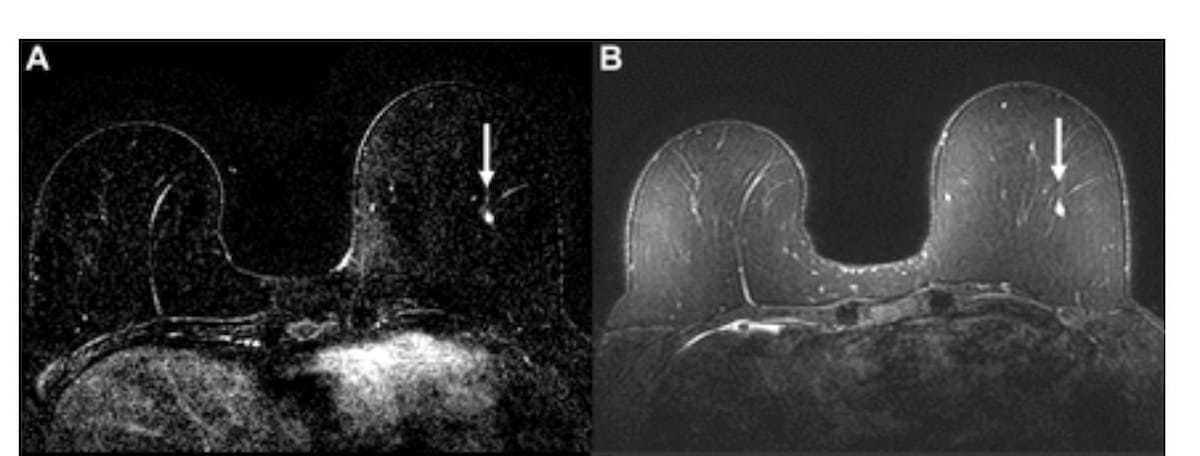

Here one can see dynamic contrast-enhanced (DCE) and fat-saturated T2-weighted MRI scans revealing an enhancing focus in the left breast for a 58-year-old woman (A and B). There was an AI score above the 50 percent threshold for suspicion with the AB-MRI but not the full MRI. While the original radiologist assessment was benign, mammogram calcifications six months later led to a diagnosis of ductal carcinoma in situ (DCIS). (Images courtesy of Radiology.)